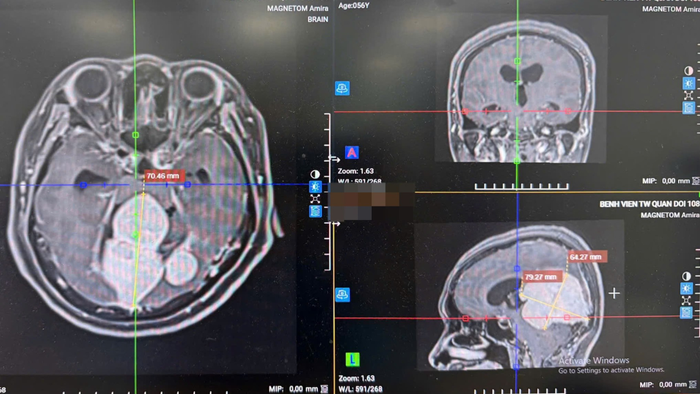

Gần đây, Bệnh viện Trung ương Quân đội 108 đã tiếp nhận một bệnh nhân nữ, 56 tuổi, với khối u màng não vùng liềm – lều tiểu não có kích thước gần 8 cm, chèn ép sâu trong nhu mô não.

Sau phẫu thuật 2 ngày, bệnh nhân tỉnh táo, không bị liệt tay chân, sức khỏe phục hồi ổn định và được chuyển về khoa hậu phẫu chăm sóc. Phim chụp MRI kiểm tra cho thấy khối u đã được lấy hết.

Phim chụp MRI trước phẫu thuật cho thấy khối u với kích thước lớn